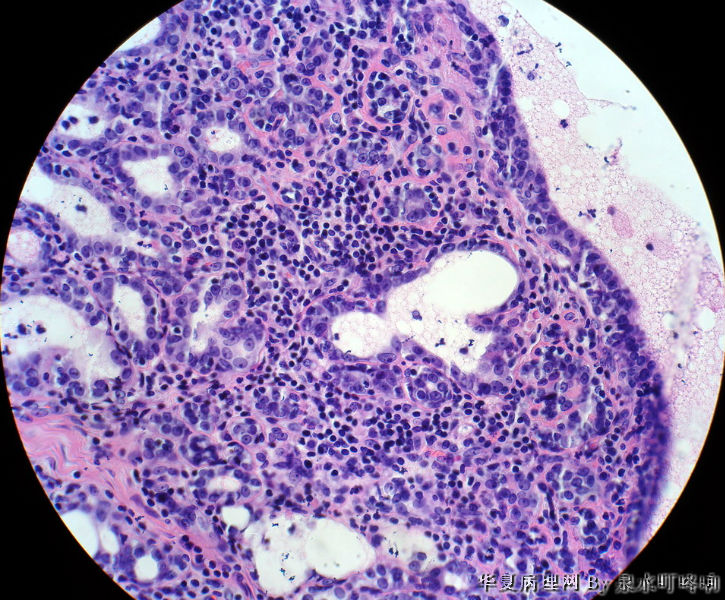

120213,女,23岁,右乳腺肿物半年,术中见肿物为多房性囊性肿物,内容黄色粘稠液体。

大体:灰白囊性肿物一个,大小约3×2×1.9厘米,局部囊壁增厚。

乳腺腺病 导管扩张囊性变 淋巴细胞性乳腺炎